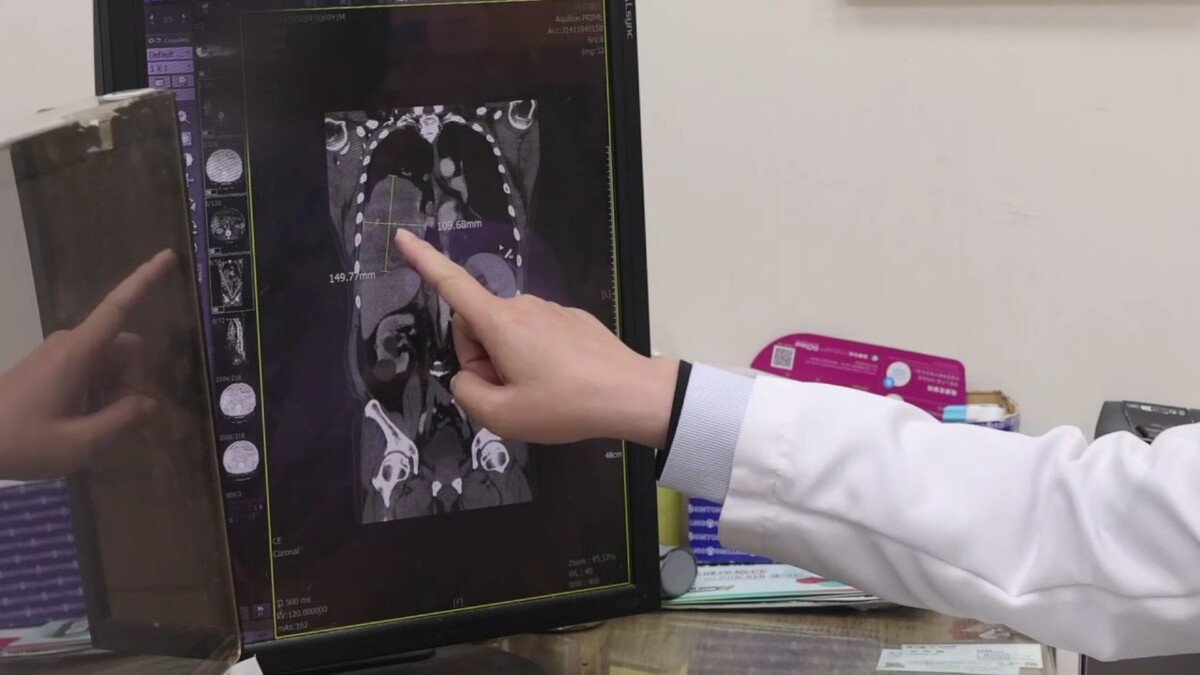

▲70歲男反覆低血糖昏迷,檢查驚見右肺15公分腫瘤,確診罕見腫瘤相關低血糖症,術後恢復良好。(員榮醫院提供)

▲70歲男反覆低血糖昏迷,檢查驚見右肺15公分腫瘤,確診罕見腫瘤相關低血糖症,術後恢復良好。(員榮醫院提供)

住院期間,患者仍頻繁發生低血糖,血糖多次低於30 mg/dL,需持續注射高濃度葡萄糖維持生命穩定。進一步胸部影像檢查發現,右肺存在一顆約15×11公分巨大腫瘤,並伴隨肋膜積液與淋巴結腫大。

院方隨即會診胸腔專科,由涂川洲參與評估,醫療團隊高度懷疑為罕見「腫瘤相關低血糖」,可能與腫瘤分泌類胰島素生長因子(IGF-2)有關,屬於非胰島素瘤性低血糖症(NICTH)。

後續跨科合作,由在員榮駐診的胸腔外科醫師 李佳穎操刀,採胸腔鏡輔助迷你開胸手術完整切除腫瘤。術後病理證實為罕見「肺部單發性纖維瘤」,約5%患者可能合併低血糖症狀。